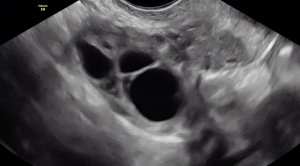

In transverse, this clip shows the right and left ovary both contain an endometrioma and the ovaries are fixed to each other medially, known as “kissing ovaries.” They are densely adherent to an area that also contains bowel deep endometriosis.